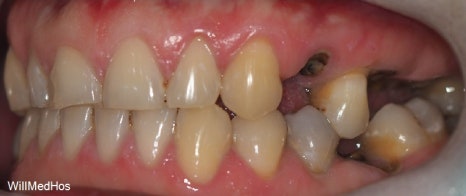

먼저 초진 구강 사진부터 보도록 하겠습니다.

▶초진 구강 사진

▲ 초진구강사진

충치로 인하여 뿌리만 남아있는 치아들과 심지어 자연 발치된 치아도 확인해 볼 수 있습니다.